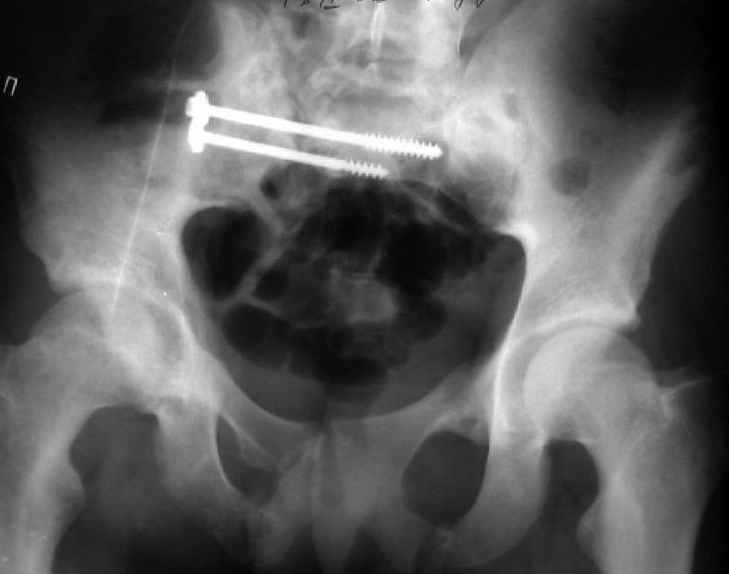

Мы, как правило, в подобных случаях проводим оперативное лечение в несколько этапов. Первым устраняем деформацию при помощи АВФ (кольцевой конструкции с фиксацией задних отделов), вторым- выполняем введение илиосакралых винтов, накостный остеосинтез передних отделов.

Для информации к размышлению о возможности исправления имеющейся деформации предлагаю похожий случай.